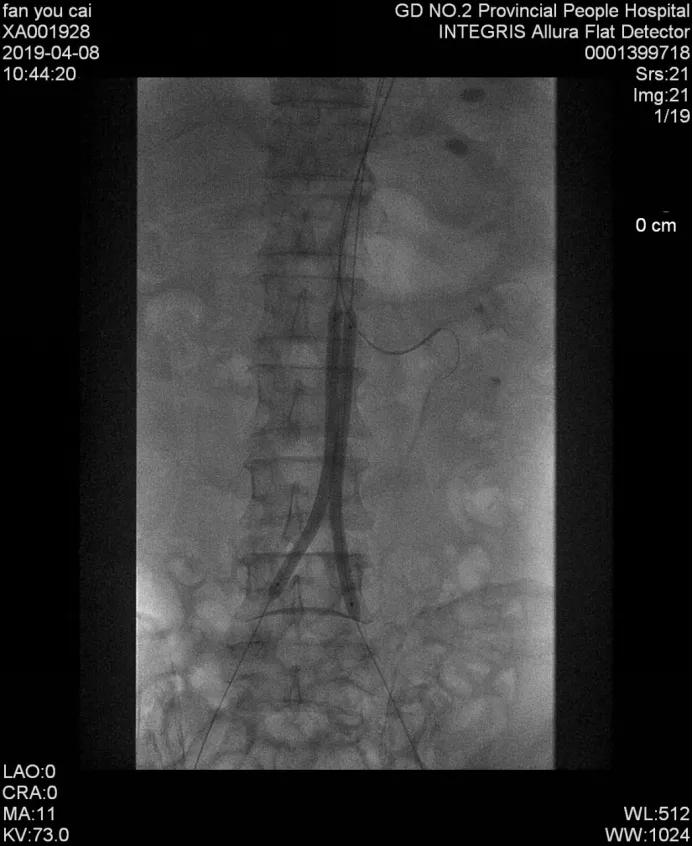

经过认真细致的讨论,最终给老樊确定了最优方案:左肾动脉、腹主动脉及髂股动脉支架植入术,手术是在一根只有针头粗的导丝引导下,将支架放入闭塞部位复通血管,不仅对患者的创伤小,而且双侧下肢可以同时进行手术,不用分两次,能省去一半的手术费用。

手术很快便安排上了,经过手术团队的努力,肖承江主任团队顺利给老樊完成了介入支架手术,术后患者腹部大血管、肾脏血管及下肢血管全部恢复通畅。